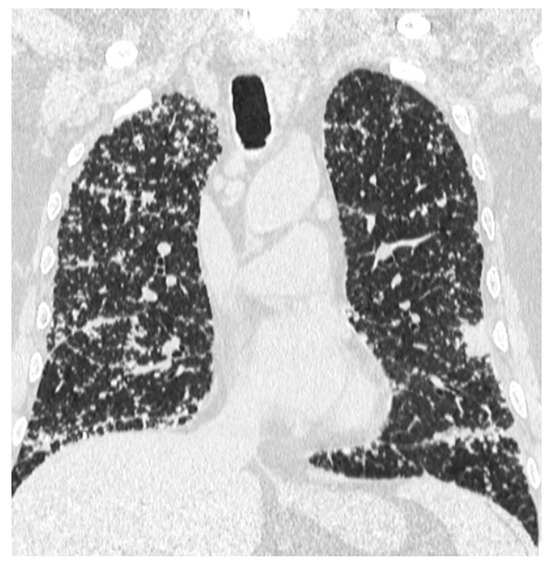

Aggressive Primary Thyroid Mucoepidermoid Carcinoma with Extensive Pulmonary Involvement

2. Case Report